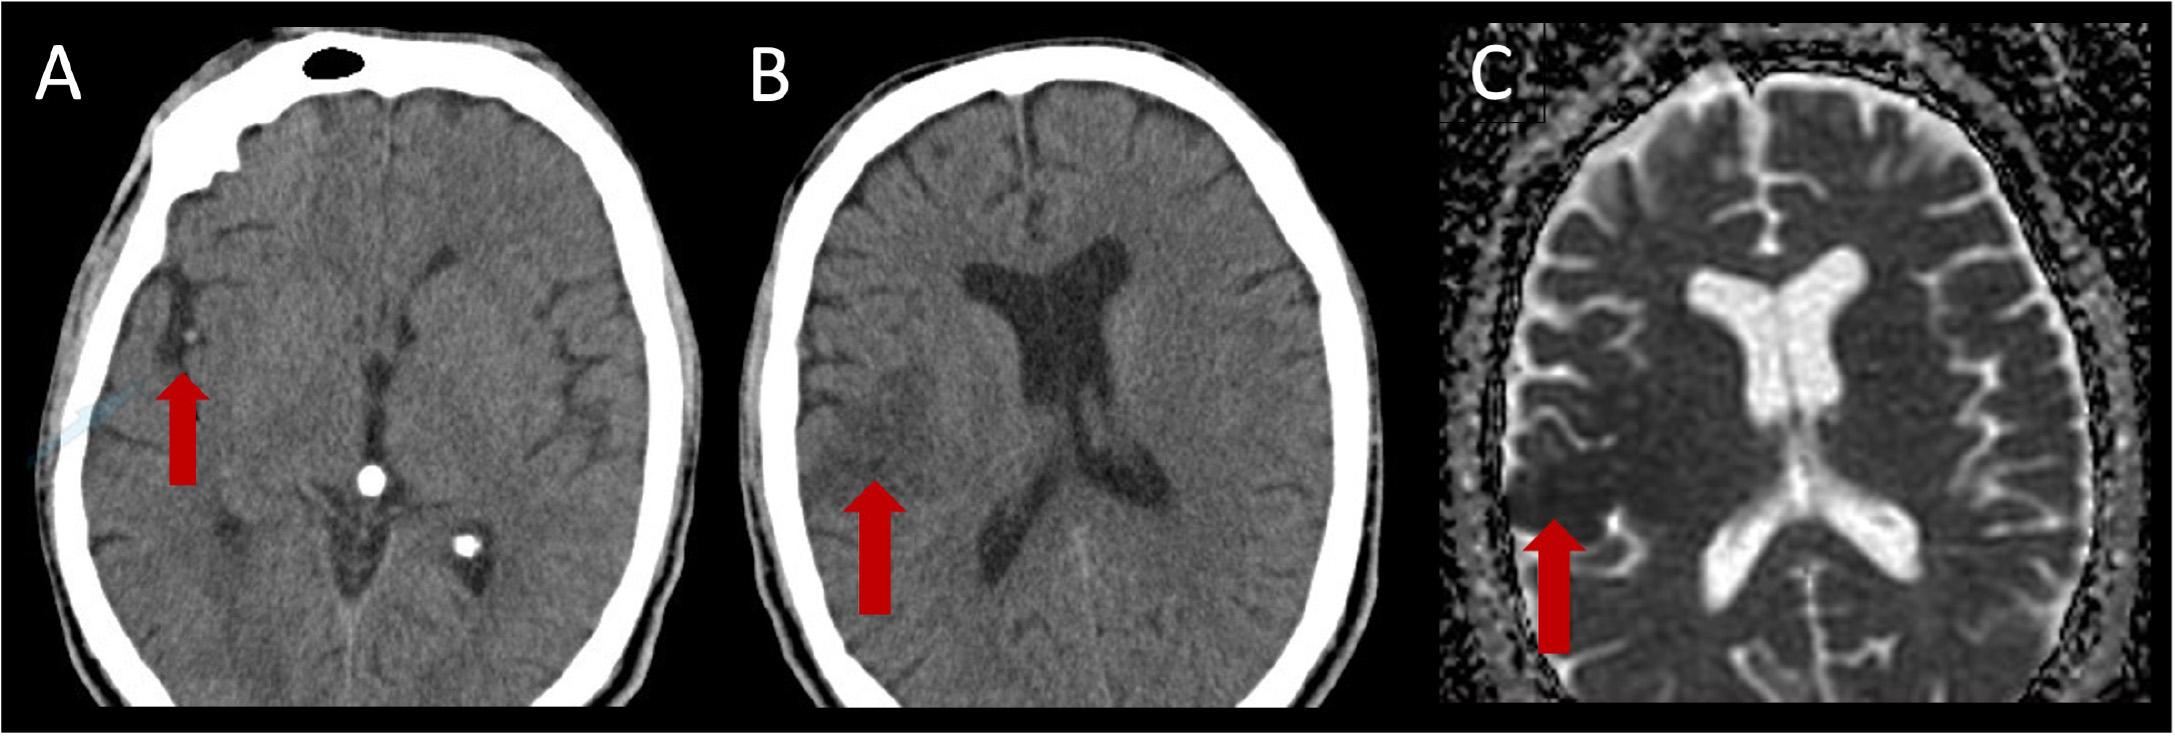

Figure 1.